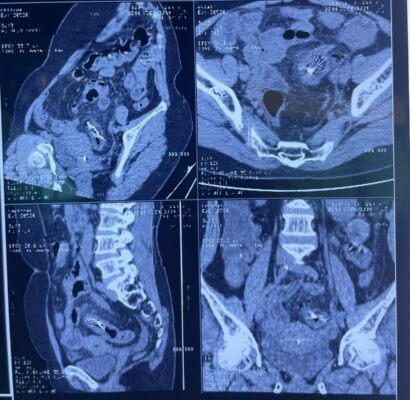

Hình 2: CT scan bụng không có thuốc cản quang: Ghi nhận dị vật dạng kim khí kích thước 60 x 4 mm, nằm tại đại tràng sigma, xuyên qua thành ruột. Mô mỡ xung quanh tăng tỷ trọng, có dấu hiệu viêm, không tụ dịch lớn. Không thấy khí tự do trong ổ bụng nhưng có dịch ổ bụng lượng ít.